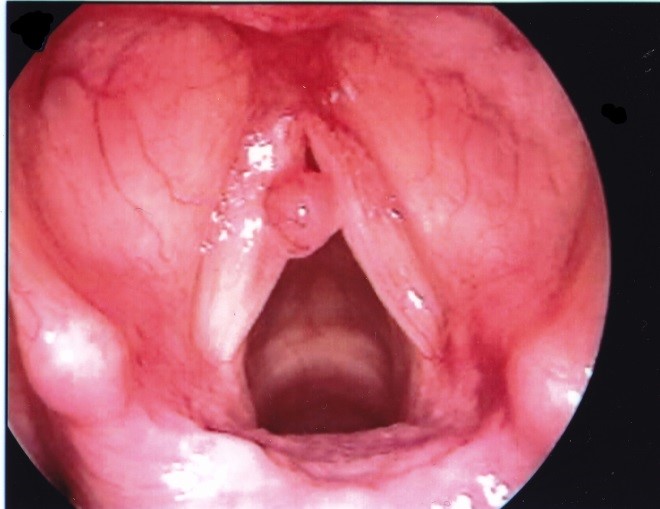

Polyps dây thanh có thể xảy ra ở 1/3 giữa dây thanh và thường một bên. Polyps có xu hướng lớn hơn và lồi hơn so với hạt xơ và thường có một mạch máu chiếm ưu thế nên màu hồng nhạt hoặc hồng đậm hơn. Chúng thường là kết quả của một thương tích ngữ âm cấp tính khởi phát. Các bệnh tích polyp khác, thường là hai bên, có thể có nhiều nguyên nhân khác, bao gồm trào ngược dạ dày thực quản, bệnh lý suy giáp chưa được điều trị, phản ứng dị ứng thanh quản mạn tính, hoặc hít chất kích thích mãn tính, như khói công nghiệp hoặc khói thuốc. Tổn thương cấp tính thường gây ra các polyp có cuống, trong khi đó viêm phù nề dây thanh là do kích ứng mãn tính.

U hạt dây thanh xảy ra ở 1/3 sau của dây thanh tương ứng với mấu thanh. Chúng có thể là hai bên hoặc một bên. Chúng thường là hậu quả của chấn thương đặt nội khí quản nhưng có thể trầm trọng thêm do bệnh trào ngược.